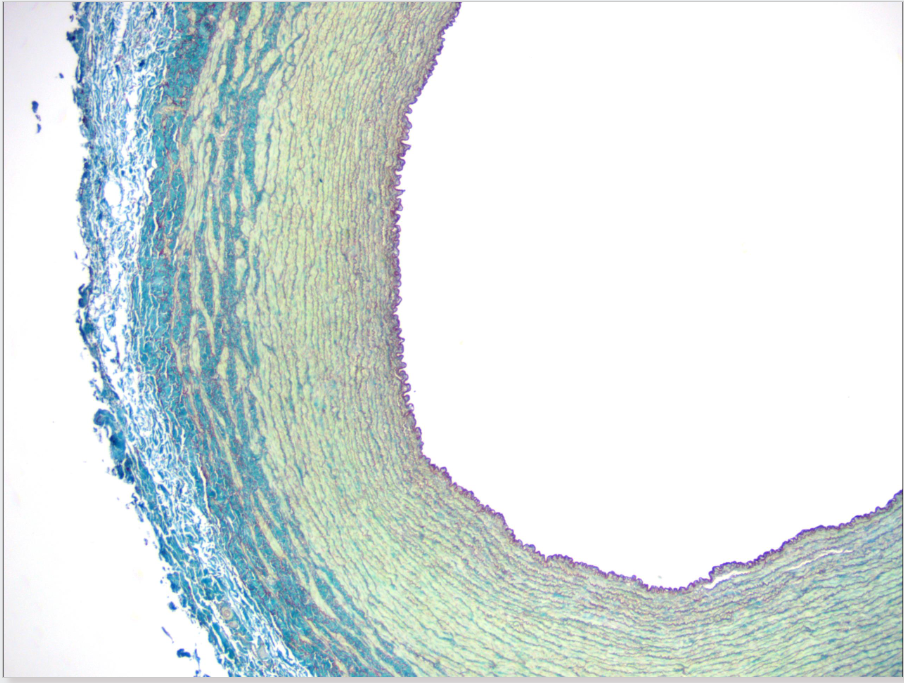

AORTA (arteria elástica)

túnica intima - teñida de rojo (orceína)

túnica media - teñida de verde (fibras elásticas)

túnica adventicia - teñida de azul (puede parecer que hay 2)

Arteria aorta (elástica)

Túnica íntima: endotelio (epitelio plano monoestratificado), subendotelio (tej conjuntivo laxo), lámina elástica interna con fenestras